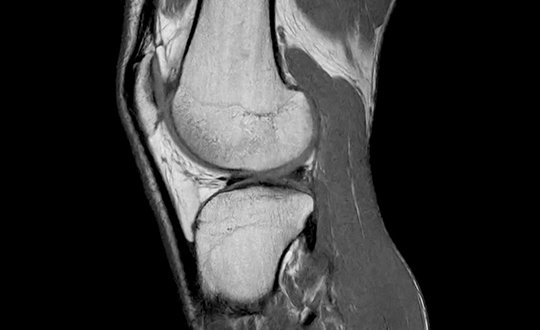

地域の先生方との連携をより強化すべく、最新の検査機器を導入しました。高精度かつ短時間での撮影を実現し、患者様の負担を軽減しながら、より明瞭な画像診断が可能となります。日常的な整形外科疾患から、より専門的な評価が必要な症例まで、地域の診療に役立つ検査体制を整えています。

1.5テスラ高磁場による高画質と、騒音を約80%低減するComforTone技術を搭載。70cmの広い開口部により圧迫感を軽減し、患者様にやさしいMRI検査を行います。

高速・高精細撮影により短時間で体内を詳しく撮影できるCT装置。80列検出器による高速撮影とAIDR 3D Enhanced技術で被ばくを低減し、安全性と精度の高い検査を行います。

関節疾患、スポーツ障害、骨折など、幅広い症例に対応可能で、患者様一人ひとりに合わせた治療方針を提案しています。術前検査から術後フォローまで一貫した対応が可能であり、地域の先生方との連携のもと、必要な症例に対し迅速かつ的確に対応します。